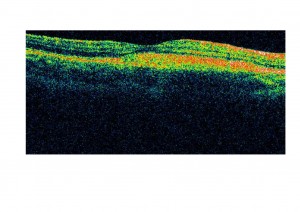

La anomalía se localiza en el cromosoma 11q13 y el gen causal es VMD2, que codifica la bestrofina, una proteína de los canales del cloro, que se localiza en la membrana plasmática de las células del epitelio pigmentario. Se cree que un transporte anómalo del cloro, motivado por las mutaciones en este gen podría alterar el transporte de líquido a través del epitelio pigmentario de la retina provocando un acúmulo de restos entre el epitelio pigmentario y los fotorreceptores de la retina y entre el epitelio pigmentario de la retina y la membrana de Bruch (como aparece en las OCT de un niño afectado de dicha enfermedad atendido en nuestra consulta).